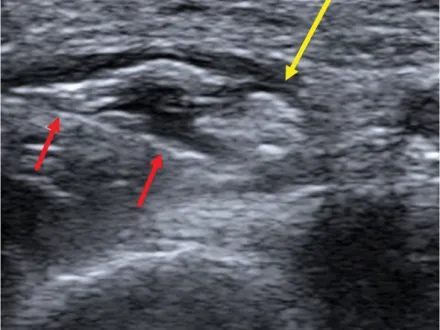

MSK Ultrasound Workshop Series: Ultrasound-Guided Nerve Hydrodissections

MSK Ultrasound Guided Nerve Hydrodissections

Presented by The New Jersey Society of PM&R